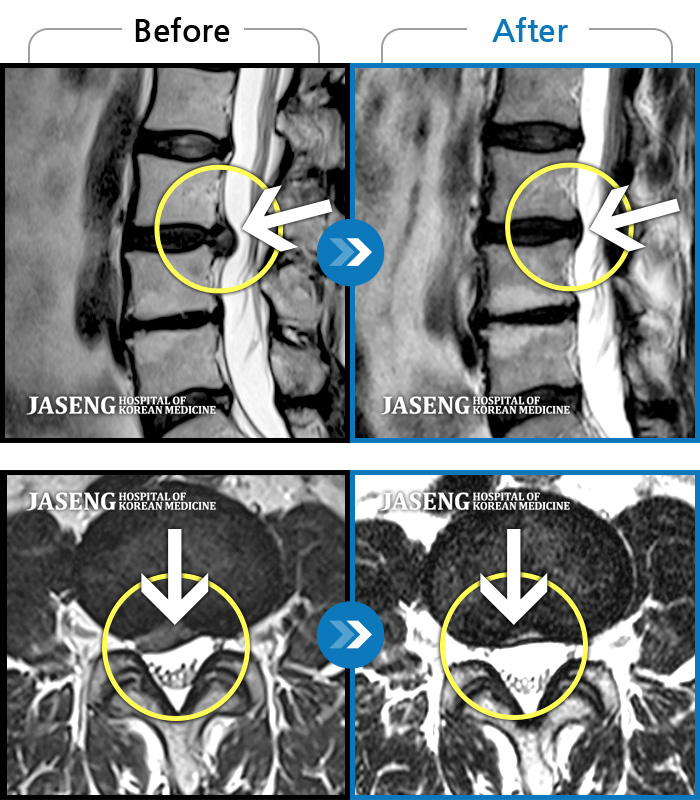

MRI로 보는 치료사례

허리디스크

많이 본 사례

강남 · 이남우 원장

허리 통증과 함께 발끝 저림이 1년 이상 되었으며 최근 1-2개월 사이에 증상이 급격히 심해져 우측 다리 앞 뒤가 당기고 힘이 빠져 본원에 내원함

촬영시기

2023.11.20 ~ 2024.08.12

2024.12.24

조회수 688